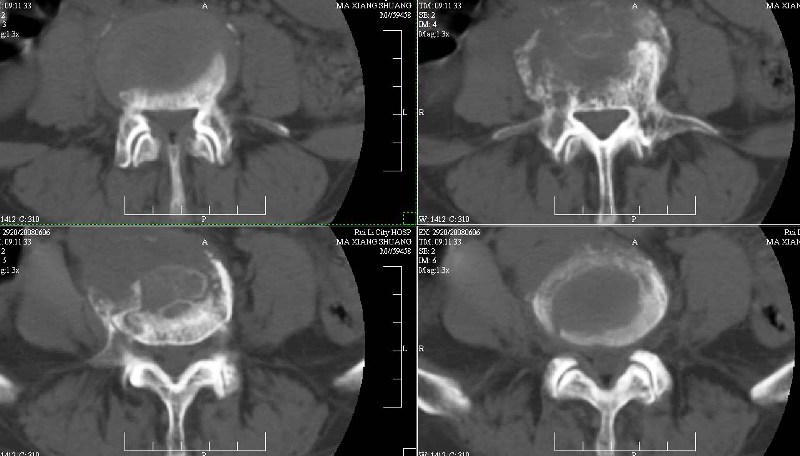

ct(椎间盘扫描):椎间盘炎,建议dr。

dr:l4骨质破坏,转移可能。